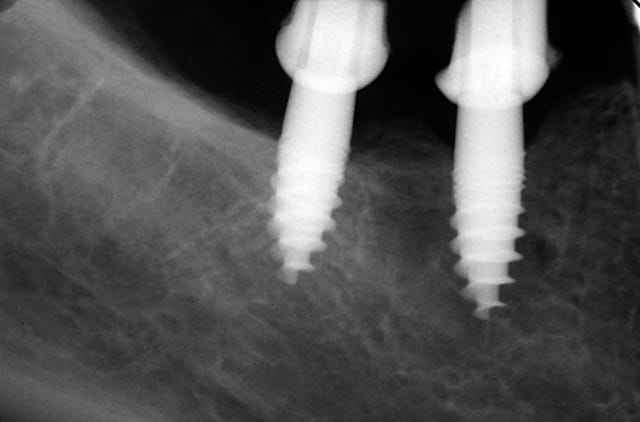

Exp dans ce cas 4,5/10mm en 36 dans un site d'extraction récent placé en 12mm soit deux millimètres plus profondément j'ai scellé un prep cap angulé 5 degrés niveau 1/0 dont la limite s'arrête à la rainure de la tête carrée, pour 37 3,5/10mm placé en 10mm j'ai utilisé un prep cap 2/2mm. On prend vite l'habitude moi j'utilise que 2 modèles en zircone et 3 en titane..

Maintenant concernant la demande de scans : je poste ce cas, une patiente vient me voir avec son scan car elle a consulté d'autres "spécialistes" et on lui refuse la pose d'implant secteur 4 où alors avec greffe préalable..Ca se discute..pas de temps à perdre je sais faire autrement..

Avec la chir trans gingivale technique MIMI ( Oui..un post sur la technique bientôt ..) j'ai pu placer deux 3,5/8mm..aurai je eu le meme résultat avec un lambeau..j'en doute..Les couronnes sont en titane. Recul clinique 2 ans ras. Simple efficace rapide moins onéreux satisfaisant pour le praticien et la patiente..